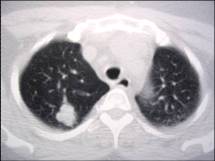

Granulomatous diseases and chronic inflammation

Needle biopsy = TB